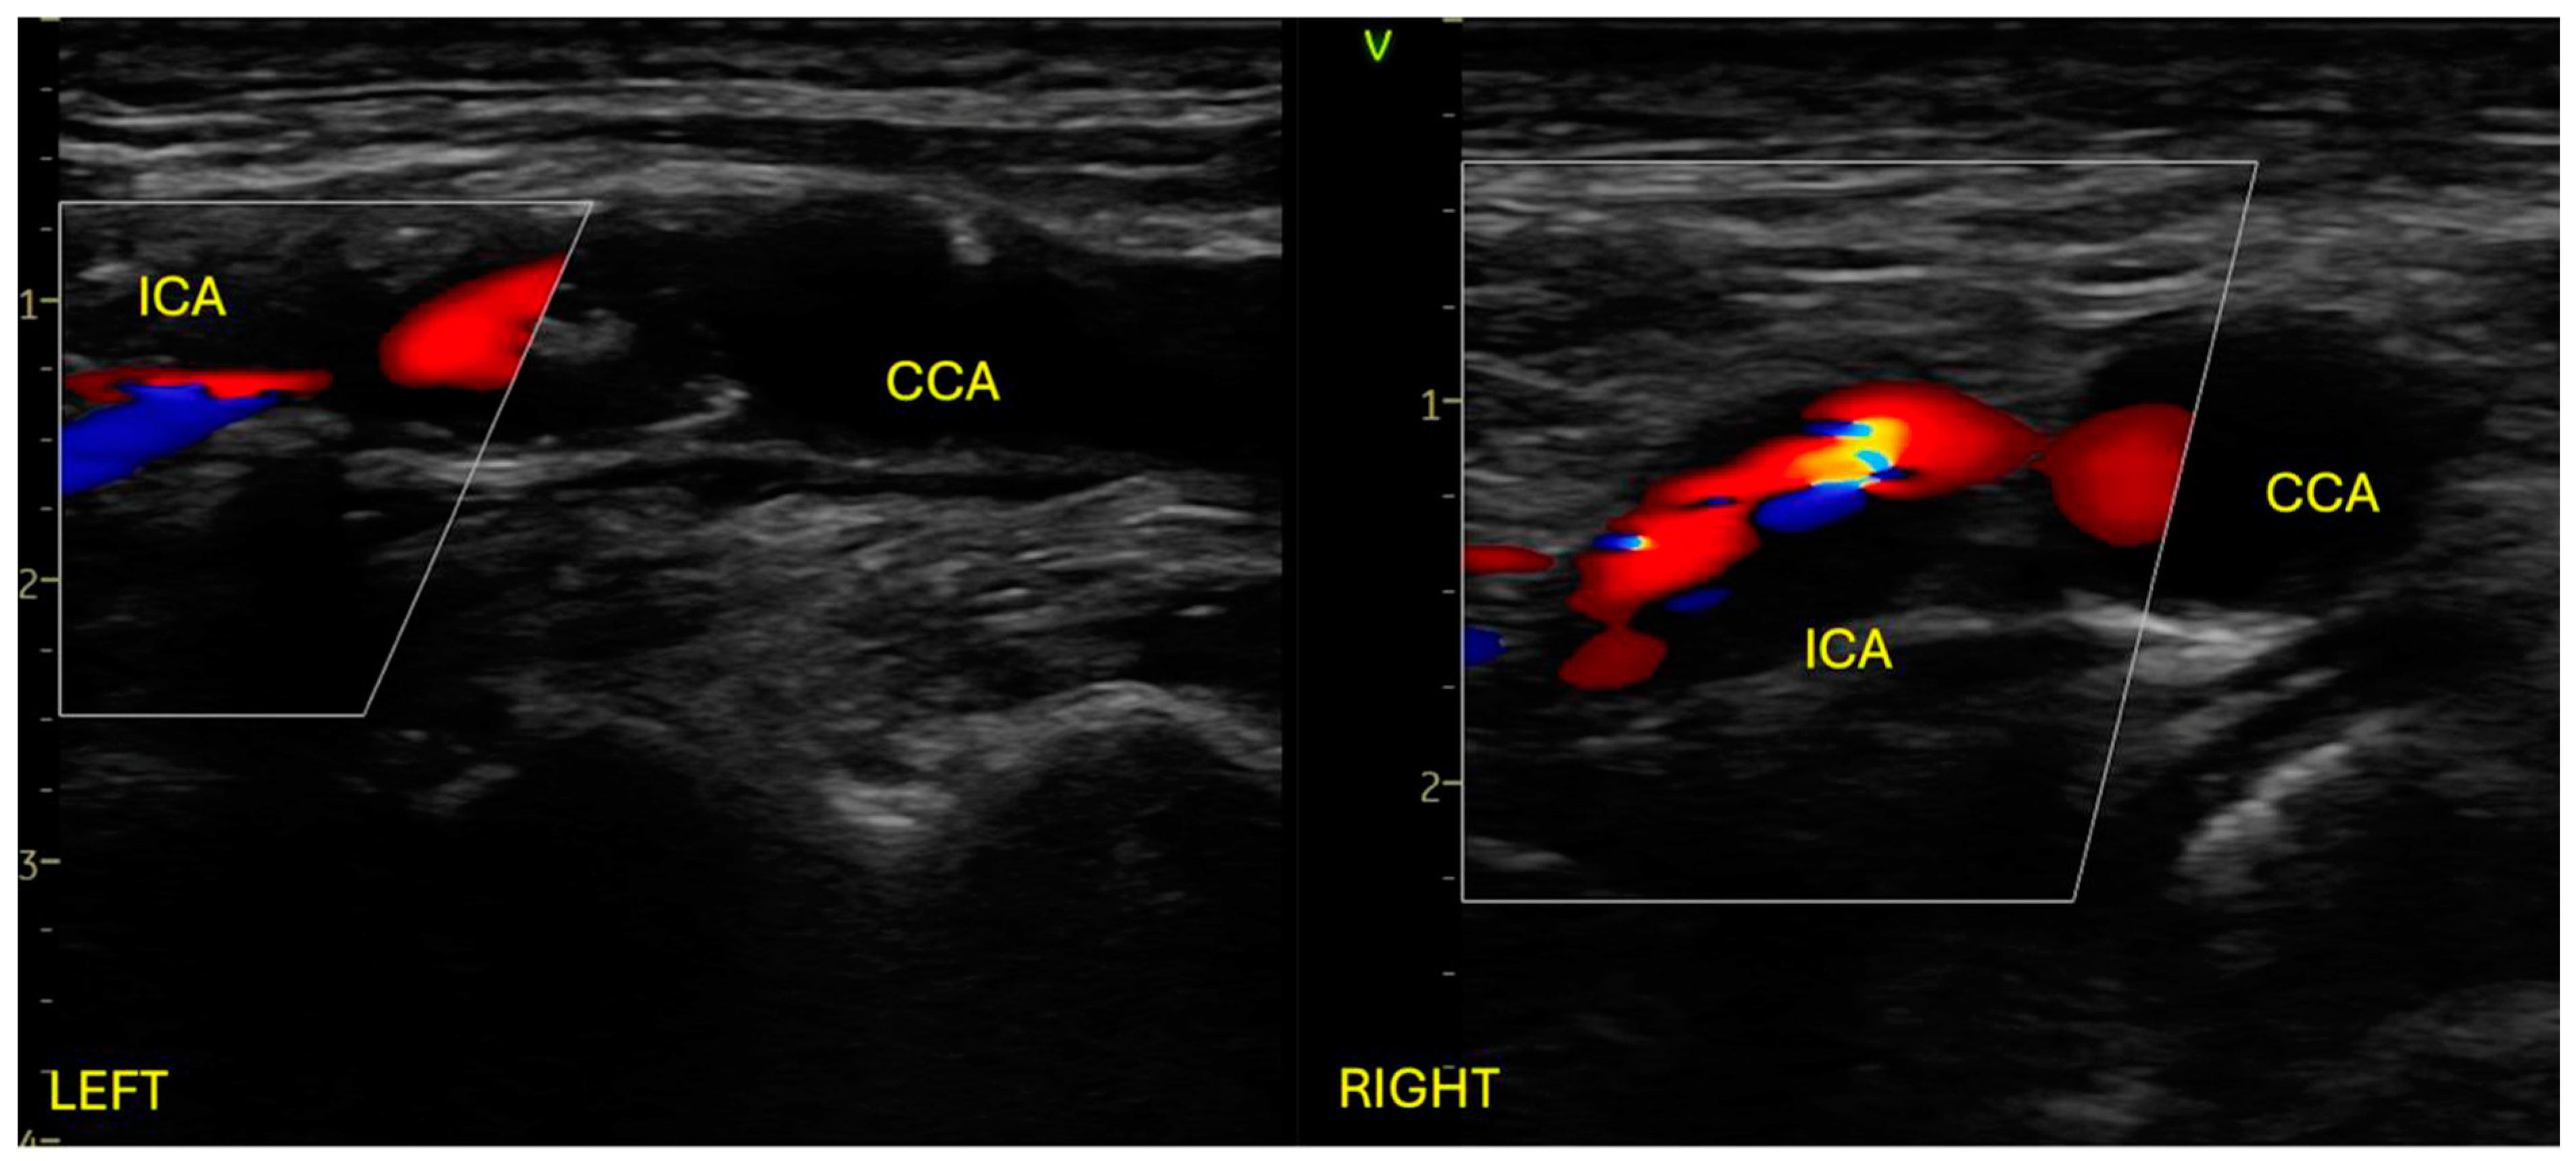

We present the case of a 64-year-old male patient with a recent history (one month) of left ACA-MCA and MCA-PCA ischemic strokes with right hemiparesis, documented on cerebral CT. A chronic frontal right ischemic lesion was also documented. Neurological examination on admission revealed right minor central facial palsy, 3/5 MRC right hemiparesis, and mild right hemihypoesthesia, consistent with an NIHSS score of 4. Past medical history revealed ischemic heart disease, with severe stenosis at the proximal level of the anterior descending artery, treated with balloon angioplasty and two drug-eluting stents 6 months before admission. Also, the patient was diagnosed with hypertension, type II diabetes, and obesity. The patient was on dual antiplatelet therapy with Aspirin and Clopidogrel. At admission, he was stable, with a 110–120 mmHg systolic blood pressure, a 95 bpm regular pulse, and a 98% peripheral oxygen saturation. He had almost complete resolution of the right hemiparesis with the rest of the clinical examination within normal limits. The blood test revealed hyperlipidemia. The EKG showed normal sinus rhythm, without any ST-T changes, and the chest XR was without any pathological findings. Transthoracic echocardiography showed normal biventricular function, no significant valvular pathology, and no pericardial effusion. Arterial Doppler ultrasound of the carotid arteries revealed 90–95% stenosis at the level of the left common carotid artery bifurcation, extending to the internal carotid artery, and 85–90% stenosis at the level of the right common carotid artery bifurcation, extending at the level of the internal carotid artery. The atheromatous plaques responsible for the severe bilateral stenosis were both of mixt echogenicity (Figure 1).

Figure 1.

Arterial Doppler ultrasound of the carotid system showing bilateral severe stenosis at the level of common carotid artery bifurcation extending at the level of the internal carotid artery. ICA: internal carotid artery; CCA: common carotid artery.